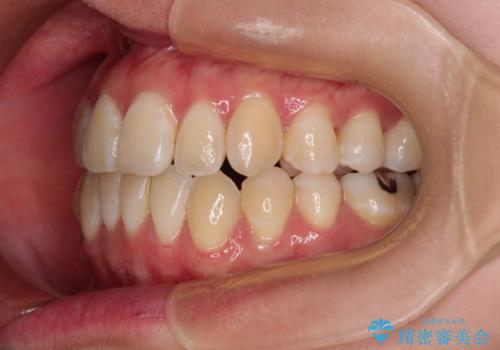

外に飛び出して磨きにくい奥歯と上下前歯の隙間 インビザラインによる矯正治療

- 上下前歯の隙間と、外側を向いていて歯磨きのしにくい奥歯を気にして来院された患者様です。

下顎前歯が1本欠損しており、上下アーチはアンバランスとなりますが、インビザラインを用いて上下の隙間を改善しながら歯列を整えることとしました。

外側を向いている奥歯は、内側にアンカースクリューを埋入して牽引の固定ゲント氏、部分的にワイヤー装置を用いることで歯列に納めることとしました。

下顎前歯の1本欠損により左右の咬合が不安定となり、治療経過で噛みにくい状態が続きましたが、最終的には違和感なく噛めるようになりました。